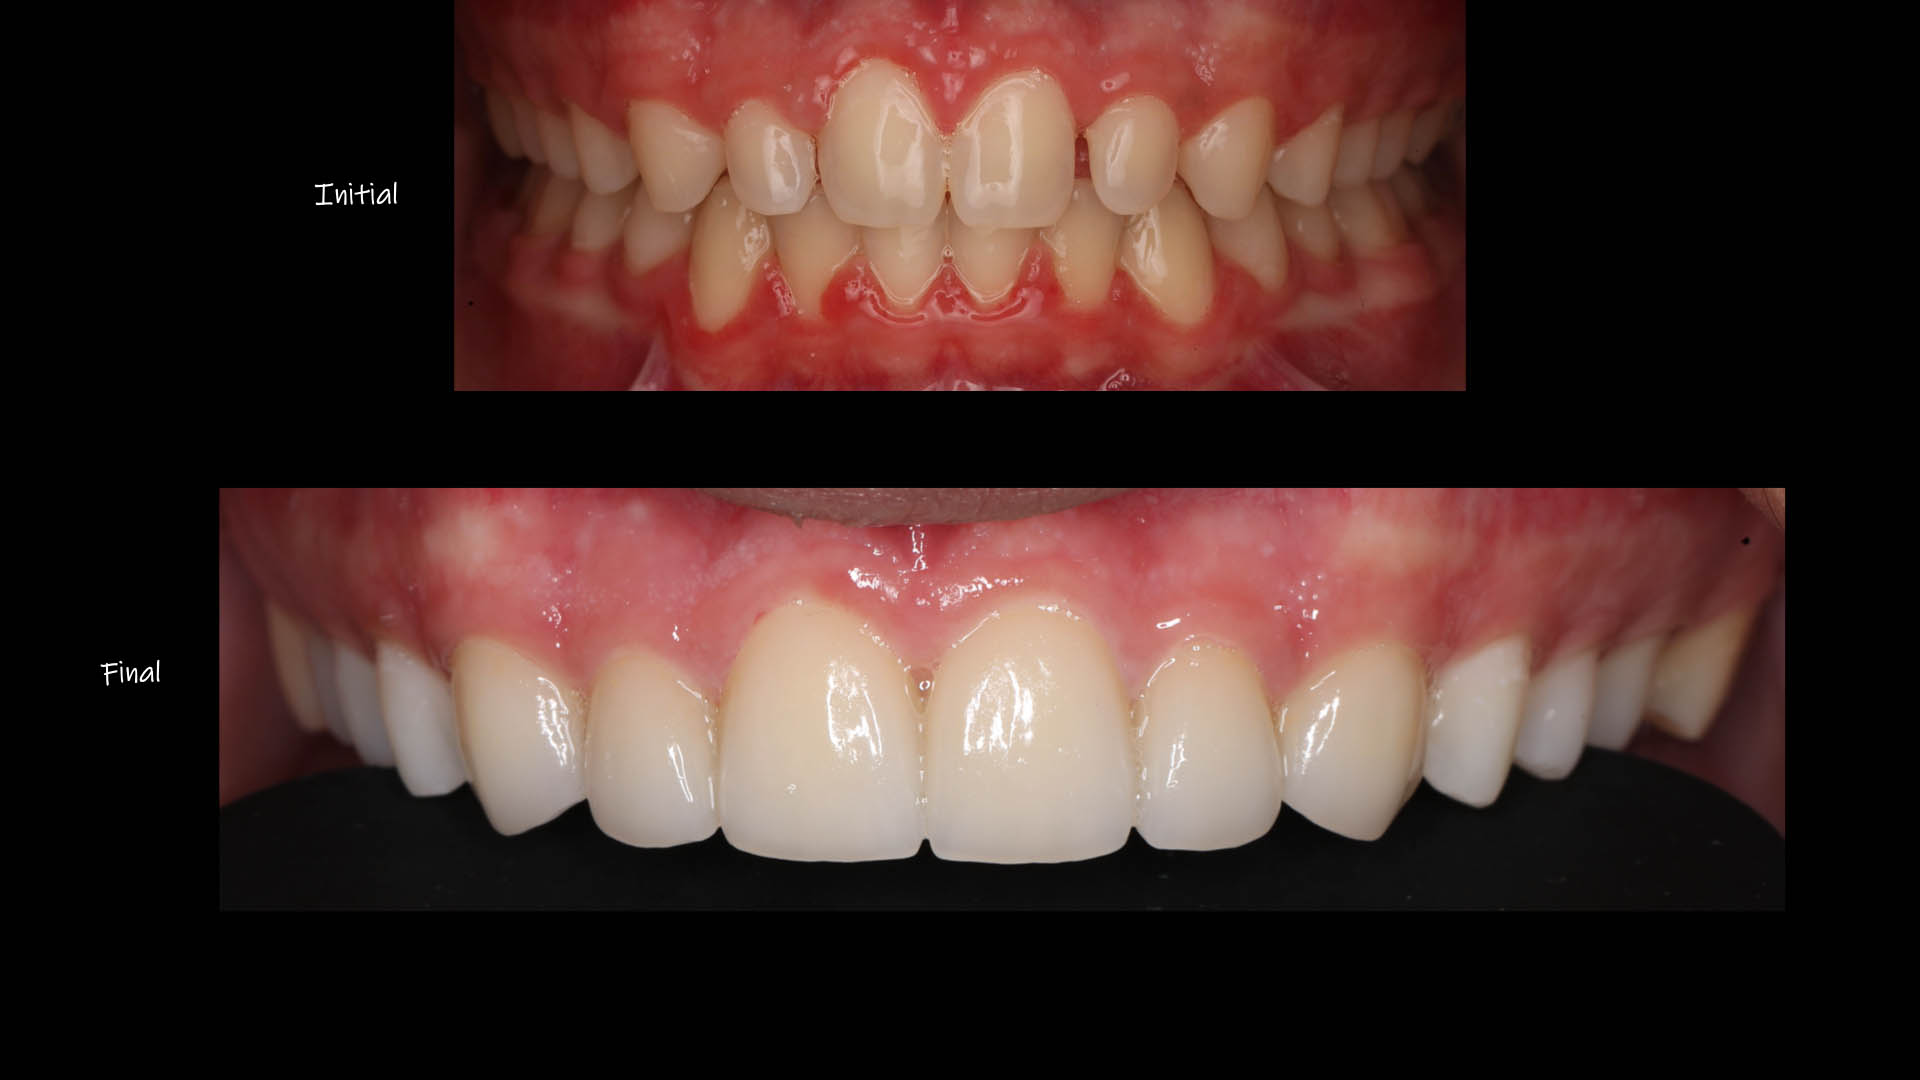

Take a glimpse into the magic of Coral Gables Dentistry through our before and after pictures. See firsthand the incredible smile makeover transformations that have brought confidence and joy to our patients.